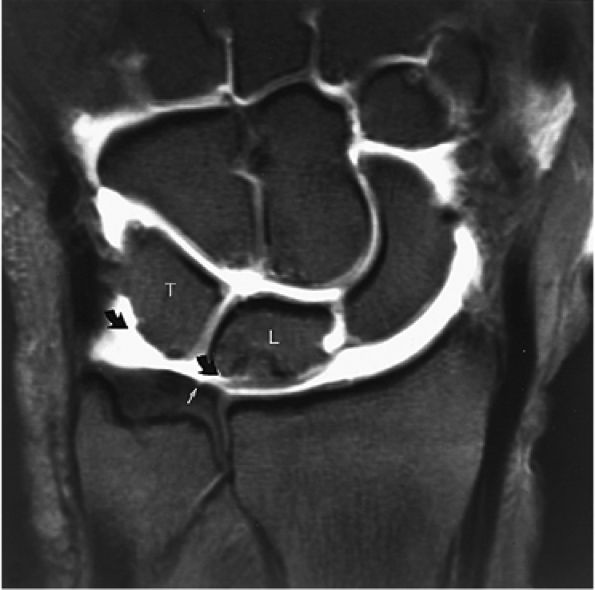

FIGURE 10.1 ● A 3D fast spoiled GRASS (FSPGR) with intra-articular contrast injected into the radiocarpal compartment. The torn lunotriquetral ligament (straight arrow) allows extension of contrast into the midcarpal compartment and the torn radial attachment of the TFC (curved arrow) directs contrast into the distal radioulnar joint. Note the superior trabecular bone detail on this image (coronal image; TR, 40.4 msec; TE, 14.5 msec; FOV, 4 cm; slice thickness, 2.0 mm; matrix, 512 × 256; flip angle, 30°).

FIGURE 10.62 ● Anatomy of the radioscaphocapitate (RSC), radiolunotriquetral (RLT), and radioscapholunate (rsl) ligaments at the level of the distal volar radius (R). T, triquetrum; S, scaphoid. FS T1-weighted arthrogram after radiocarpal injection.